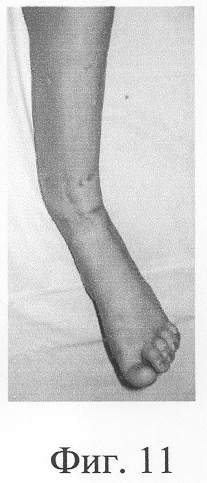

Больная П., 42 лет, поступила для оперативного лечения с диагнозом «атрофические ложные суставы обеих большеберцовых костей; сросшийся с укорочением 5 см перелом левой бедренной кости, хронический остеомиелит левой бедренной кости, фаза ремиссия; посттравматическая невропатия правого малоберцового нерва». В анамнезе – накостный, а затем дважды внеочаговый остеосинтез левой большеберцовой кости с исходом в ложный сустав; 4 операции внеочагового остеосинтеза правой большеберцовой кости, в том числе с костной пластикой; сроки фиксации в аппарате от 5 до 10 мес. Результат не достигнут: с обеих сторон сформировались ложные суставы (фиг.8-11 – клинические и фиг.12-15 – рентгенологические данные до лечения по предложенному методу).

Одномоментно выполнены операции: резекция ложных суставов обеих большеберцовых костей, резекция левой малоберцовой кости, комбинированный чрескостный остеосинтез костей обеих голеней, костная пластика ложных суставов деминерализованным костным аллотрансплантатом из трубчатой кости, предварительно в лабораторных условиях заселенным аутологичными мезенхимными стволовыми клетками, выделенными из костного мозга пациентки, с плотностью заселения 7-10 млн на 1 см3 трансплантата. В послеоперационном периоде потребовалась дополнительная коррекция положения фрагментов на правой голени, что привело к смещению трансплантата из костного паза. Дренажи удалены на 3-е сутки, швы сняты на 15 сутки, антибактериальная терапия под контролем клинического фармаколога с учетом анамнеза. Ходьба с дополнительными средствами опоры с 7 суток послеоперационного периода. Компенсация укорочения бедра обувью (фиг.16-17 – клинические и фиг.18-19 – рентгенологические данные в процессе лечения, трансплантаты отчетливо видны на рентгенограммах, отмечается нарастание плотности костной ткани в области трансплантатов).

Аппарат внешней фиксации с левой голени демонтирован через 3 месяца после операции при клинико-рентгенологической картине сращения перелома. Аппарат внешней фиксации с правой голени демонтирован через 7 месяцев после операции при клинико-рентгенологической картине сращения перелома (фиг.20-25 – результат лечения). При рентгенологическом и томографическом контроле в трансплантатах отмечалось постепенное нарастание плотности костной ткани с формированием костной мозоли на всем протяжении между трансплантатом и костными фрагментами (фиг.26-29 – динамика данных компьютерной томографии правой голени: отмечается нарастание плотности костной ткани в области трансплантатов и формирование регенерата между смещенным трансплантатом и костными фрагментами; фиг.30-33 – динамика данных компьютерной томографии левой голени: отмечается нарастание плотности костной ткани в области трансплантатов и формирование регенерата между трансплантатом и костными фрагментами).